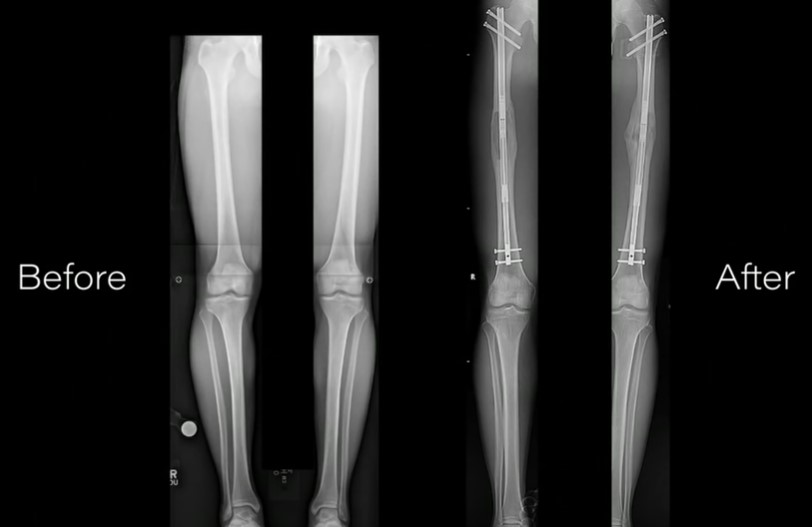

Extinderea picioarelor este o procedură care presupune ruperea ambelor femururi (partea de sus a piciorului) după care se introduce în ele o tijă de metal ținută cu un număr de șuruburi. Aceasta este lungită cu un milimetru în fiecare zi până când pacientul ajunge la înălțimea dorită, iar oasele pot concrește. Unii curajoși pot atinge o creștere între 7 și 15 centimetri, dacă se hotărăsc să își lungească și tibia (partea de jos a piciorului), pe lângă femur.

După operație este nevoie de câteva luni de reabilitare pentru dezvoltarea mobilității, iar unii pacienți sunt nevoiți să învețe din nou să meargă. Uneori operația este însoțită de complicații și chiar riscul ca oasele să nu fuzioneze la loc. Iar pe lângă oase, este nevoie și de creșterea mușchilor, nervilor, vaselor de sânge și a pielii.